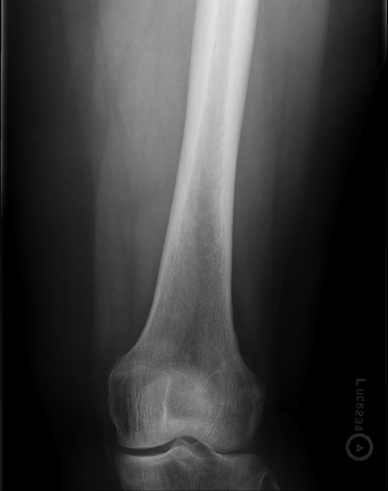

Trauma and Non Trauma AP Knee

•Evidence of proper collimation and the presence of a side marker placed clear of the anatomy of interest

•Knee fully extended if patient’s condition permits

•Entire knee without rotation

•Femoral condyles symmetric and tibia intercondylar eminence centered

•Slight superimposition of the fibular head if the tibia is normal

•Patella completely superimposed on the femur

•Open femorotibial joint space, with interspaces of equal width on both sides if the knee is normal

•Bony trabecular detail and surrounding soft tissues

Anatomy of the knee

Lateral Rotation, the fibular head is under the tibia, if patella is towards lateral side usually means it is laterally rotated.

Joint space is not open enough

The width of the joint space is not equal

REPEAT FOR LATERAL ROTATION

Not enough superimposition of the fibular head

Patella is in the center! good! equal distance of joint space/platoes which is good

ACCEPTABLE BECAUSE EVERYTHING ELSE IS GOOD! PATIENT COULD HAVE A MORE SEPARATED FIBULAR HEAD! THEIR ANATOMY IS DIFFERENT. CENTERING IS GOOD